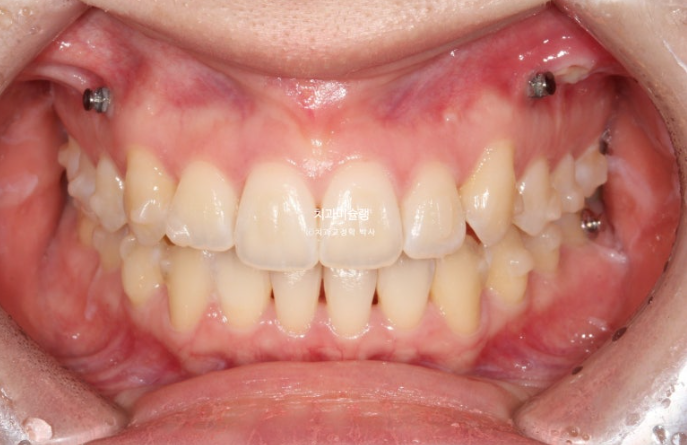

정면사진에서 블랙트라이앵글, 중심선 불일치 등이 보입니다.

덧니쪽으로 중심선은 치우치기 마련이지만 그 이외에도 양쪽 어금니 교합관계가 다르다 보니 중심선 불일치가 크게 나타납니다.

2급 교합관계를 보이는 좌측엔 교합관계 개선을 위한 악간고무줄 처방을 해서 덧니뿐아니라 교합관계개선과 주심선 개선을 도모합니다.

또한 웃을때 잇몸도 보이는 편이라 교정용 나사를 심고 앞니 함입도 도모했습니다.